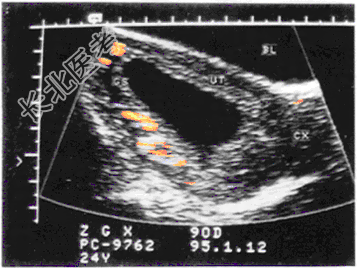

- 单项选择题女,25岁, 停经55天,腹痛、阴道出血1周。尿妊娠试验阴性。结合超声图像, 最可能的诊断为

A、正常早孕

B、完全流产

C、先兆流产

D、难免流产

E、宫腔积液尿HCG阴性